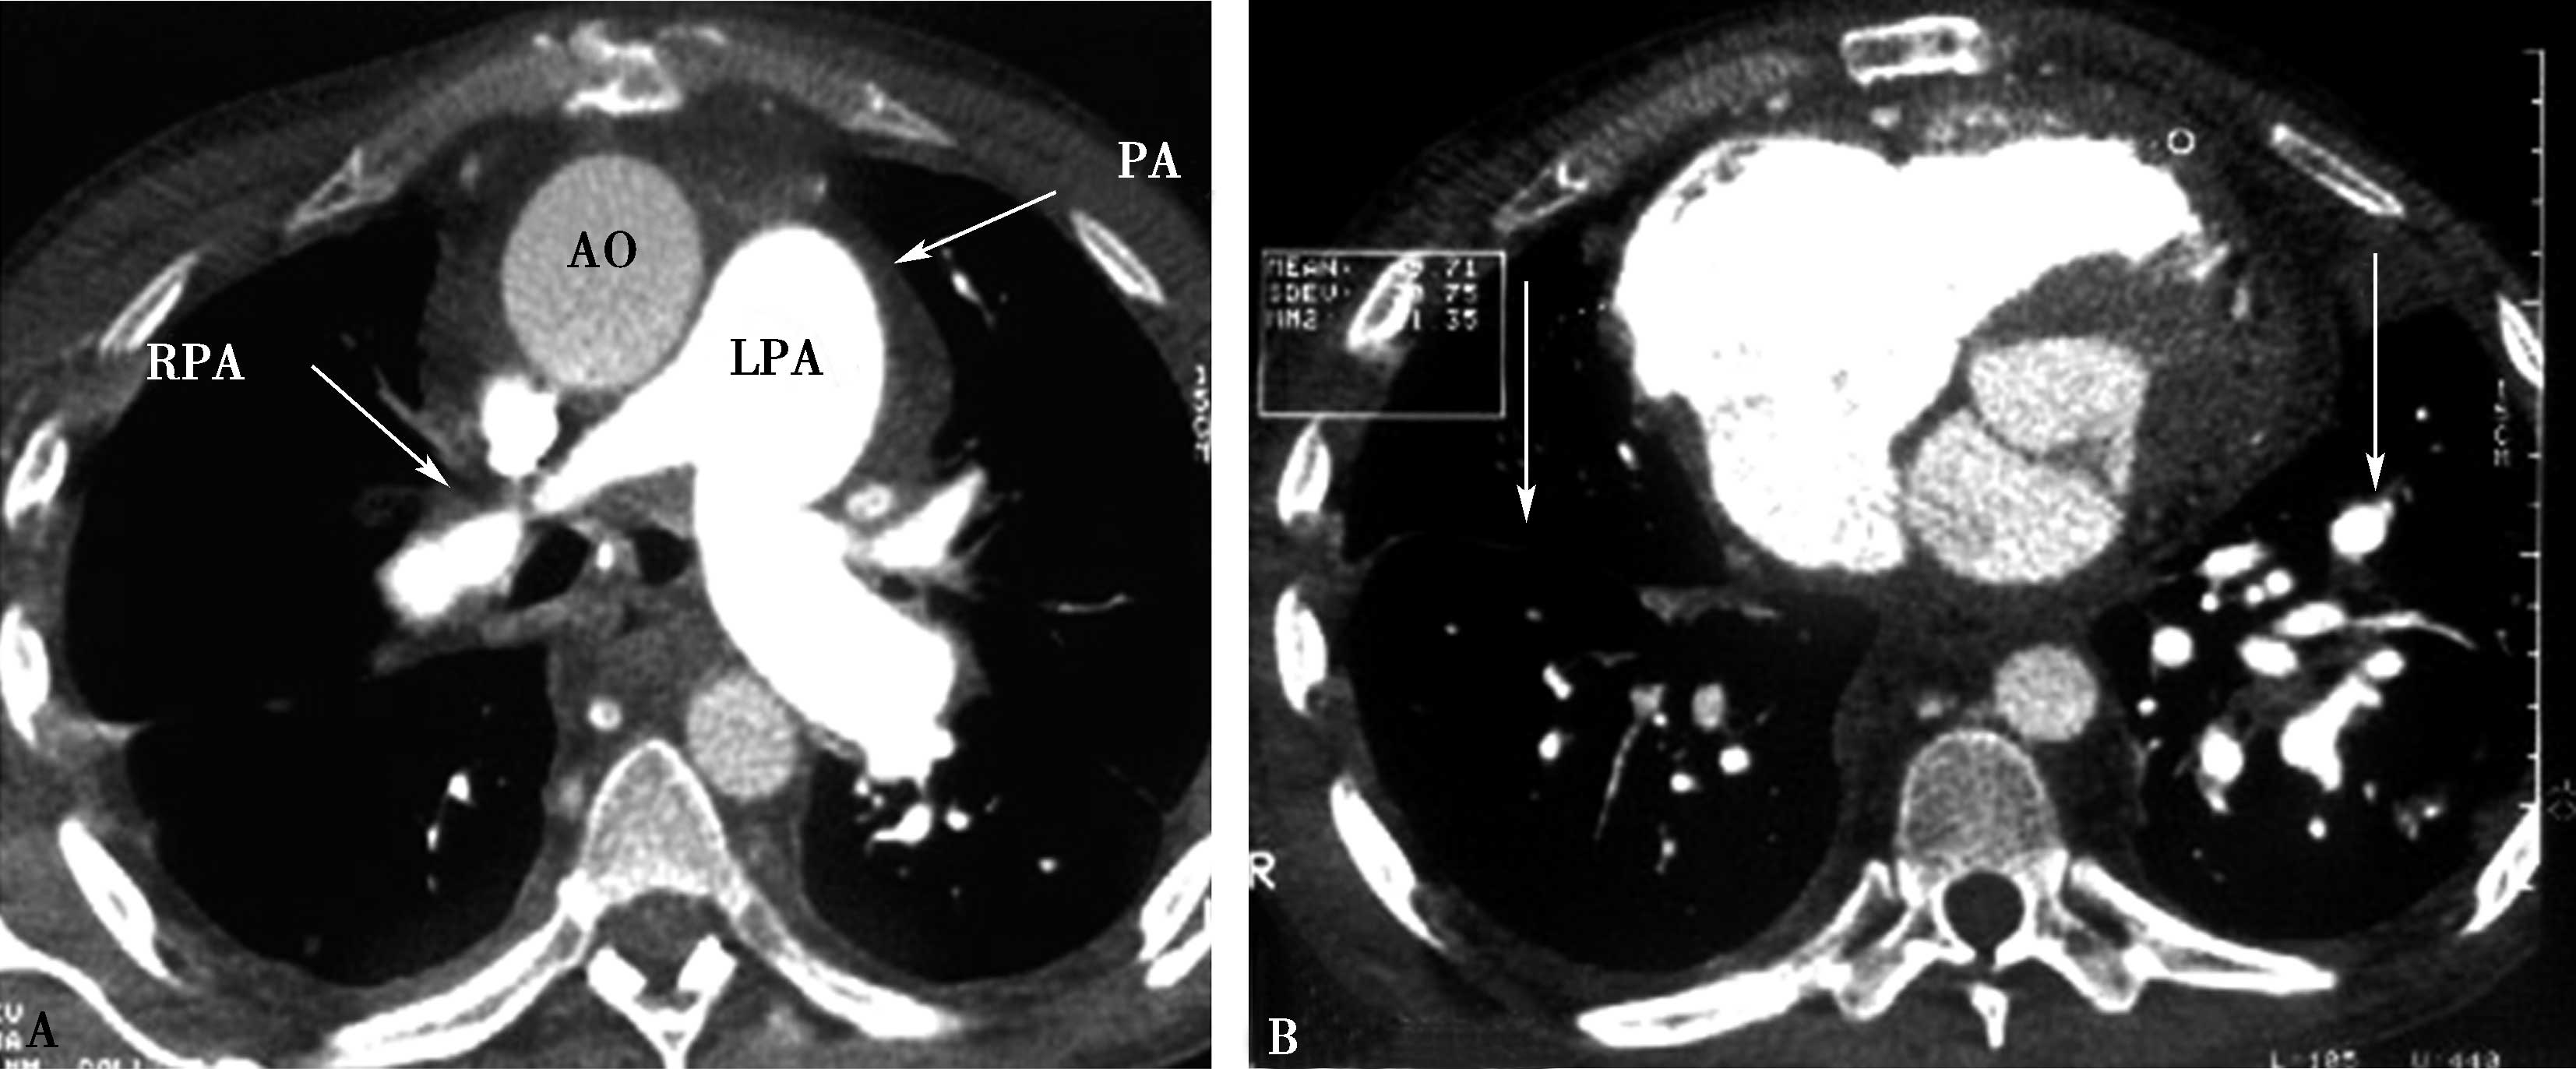

图8-6-1 缩窄性心包炎、纵隔炎(结核性),心包缩窄术后

A、B.横断图像,右肺动脉被纵隔纤维化包围重度狭窄-闭塞(A↑);右侧肺血少(B↑),左侧肺血多(B↑);肺动脉高压,右心房扩大。AO:升主动脉;PA:肺动脉;RPA:右肺动脉;LPA:左肺动脉

图8-6-2 男,34岁,慢性纵隔炎(结核性)肺动脉、主动脉受累,肺动脉高压

A、B.横断扫描纵隔增宽,纵隔胸膜增厚,主动脉与肺动脉间低密度脂肪间隙消失,代之以中等密度(结缔组织),主动脉、主肺动脉及左右肺动脉外形不规则,粗细不均,钙化。主肺动脉及右肺动脉狭窄为主,左肺动脉瘤样扩张;C、D.肺动脉三维重建,示主肺动脉及右肺动脉粗细不均,不规则狭窄,主肺动脉瘤扩张。PA:主肺动脉;LPA:主肺动脉;RPA:右肺动脉;AO:升主动脉

(一)横断扫描

胸部平扫及增强扫描显示纵隔增宽,纵隔胸膜增厚,器官间(如大血管、气管、食管)低密度脂肪间隙消失,代之以中等密度结缔组织。主动脉、肺动脉外形不规则,粗细不均,管壁钙化,大气管、食管狭窄。

肺动脉受累表现为主肺动脉及左右肺动脉外形不规则,粗细不均,不同程度狭窄-闭塞、与瘤样扩张交替出现;管壁钙化;可以出现肺动脉高压征象,右心房室扩大(图8-6-1,图8-6-2)。